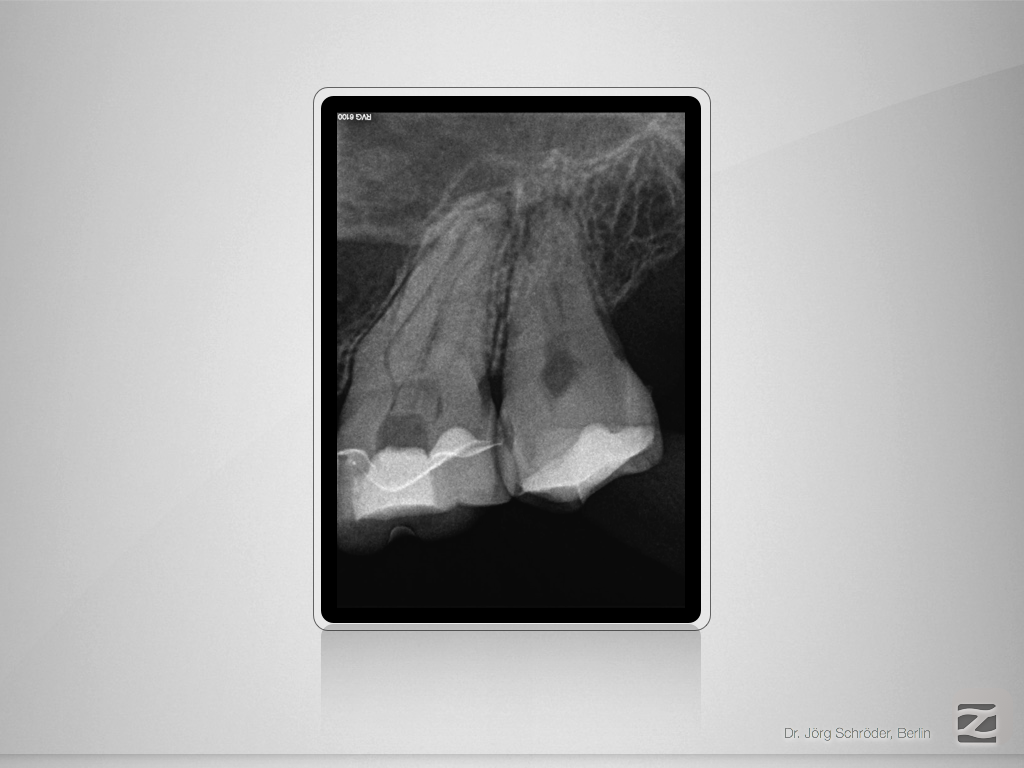

Mutter aller Dentikel